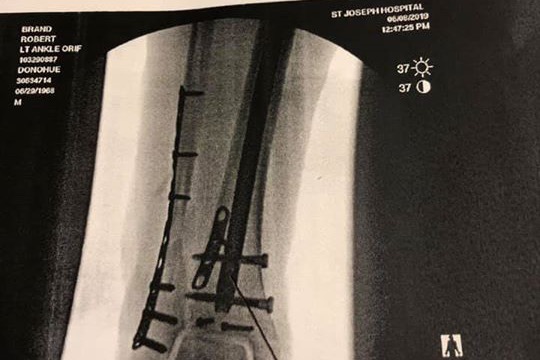

Life seems to make life interesting, after planning my 50th Birthday trip aboard the Cayman Aggressor last year, I was unable to make it. So this year, I rescheduled and had several friends sign up to go with me on this adventure. Unfortunately, I had a very bad, freakish accident recently and broke my lower leg and ankle in FOUR places, yes four places! Per the Orthopedic MD, I can not walk/weight bear on it, let alone dive, for the next 3 months! I do have trip insurance but it did not cover this kind of cancellation, optional option coverage if you understand, so i am trying this Go Fund Me idea at a request of a friend, more importanly, I am also doing this to cover my time out of work and some extra medical expenses that I have incurred. This is the busy time of year for scuba instructors so if we are not working, we are not making money. I have a strong group of friends helping with my immediate financial, medical and yes housing needs, but this is a long term issue. I am side lined for 3 months, will lose out on the 2019 dive season. So any help will be great to help me get through the slow winter season, get back on my feet ( foot) and into the water to do what i love!

Life seems to make life interesting, after planning my 50th Birthday trip aboard the Cayman Aggressor last year, I was unable to make it. So this year, I rescheduled and had several friends sign up to go with me on this adventure. Unfortunately, I had a very bad, freakish accident recently and broke my lower leg and ankle in FOUR places, yes four places! Per the Orthopedic MD, I can not walk/weight bear on it, let alone dive, for the next 3 months! I do have trip insurance but it did not cover this kind of cancellation, optional option coverage if you understand, so i am trying this Go Fund Me idea at a request of a friend, more importanly, I am also doing this to cover my time out of work and some extra medical expenses that I have incurred. This is the busy time of year for scuba instructors so if we are not working, we are not making money. I have a strong group of friends helping with my immediate financial, medical and yes housing needs, but this is a long term issue. I am side lined for 3 months, will lose out on the 2019 dive season. So any help will be great to help me get through the slow winter season, get back on my feet ( foot) and into the water to do what i love!

Life seems to make life interesting, after planning my 50th Birthday trip aboard the Cayman Aggressor last year, I was unable to make it. So this year, I rescheduled and had several friends sign up to go with me on this adventure. Unfortunately, I had a very bad, freakish accident recently and broke my lower leg and ankle in FOUR places, yes four places! Per the Orthopedic MD, I can not walk/weight bear on it, let alone dive, for the next 3 months! I do have trip insurance but it did not cover this kind of cancellation, optional option coverage if you understand, so i am trying this Go Fund Me idea at a request of a friend, more importanly, I am also doing this to cover my time out of work and some extra medical expenses that I have incurred. This is the busy time of year for scuba instructors so if we are not working, we are not making money. I have a strong group of friends helping with my immediate financial, medical and yes housing needs, but this is a long term issue. I am side lined for 3 months, will lose out on the 2019 dive season. So any help will be great to help me get through the slow winter season, get back on my feet ( foot) and into the water to do what i love!